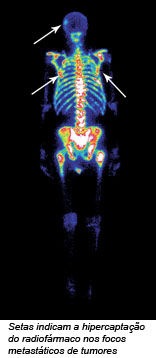

O principal radioisótopo utilizado no diagnóstico de várias doenças é o [99mTc] tecnécio, que é capaz de formar complexo organometálico com um grande número de ligantes. Como exemplos temos: o [[99mTc](OH)2 (MDP)2]2-, utilizado na cintilografia óssea (Na figura ao lado, as setas indicam a hipercaptação do radiofármaco nos focos metastáticos de tumores); o [[99mTc] O(ECD)], utilizado em estudos de perfusão cerebral, permitindo detectar doenças com Alzheimer, epilepsia e outras alterações no fluxo e metabolismo cerebral; [[99mTc] (MIBI)6]+, utilizado em estudos de perfusão do miocárdio permitindo localizar regiões de isquemia antes que ocorra um infarto.